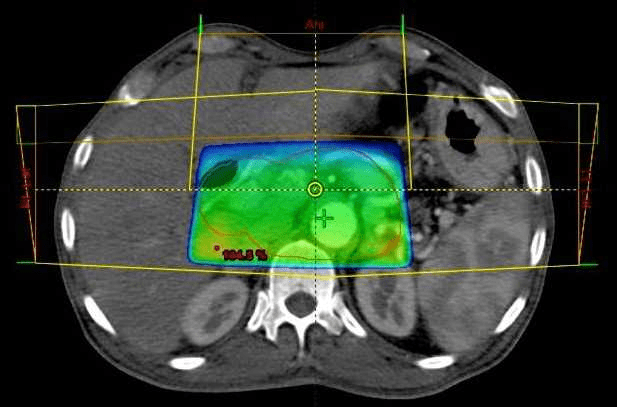

La radioterapia conformada tridimensional, uno de los tantos tipos de radioterapia, es una técnica que permite que los médicos dirijan haces de radiación que se adapten a la forma del tumor.

En comparación con la radioterapia bidimensional, la radioterapia conformada tridimensional envía radiación a las células cancerosas con mayor precisión mientras reduce la cantidad de radiación a las células sanas. Esta forma convencional de radioterapia se utiliza para tratar tumores cancerosos y no cancerosos en todo el cuerpo.

A fin de prepararse para una radioterapia conformada tridimensional, los especialistas utilizan tecnología de avanzada para diagramar la trayectoria de los múltiples haces de radiación que se apuntarán al tumor desde diferentes direcciones. Durante la radioterapia conformada tridimensional, los haces envían una dosis fija de tratamiento al tumor, que se disemina alrededor del tejido normal que lo rodea para minimizar la dosis de entrada y de salida que se aplica a cualquier área.